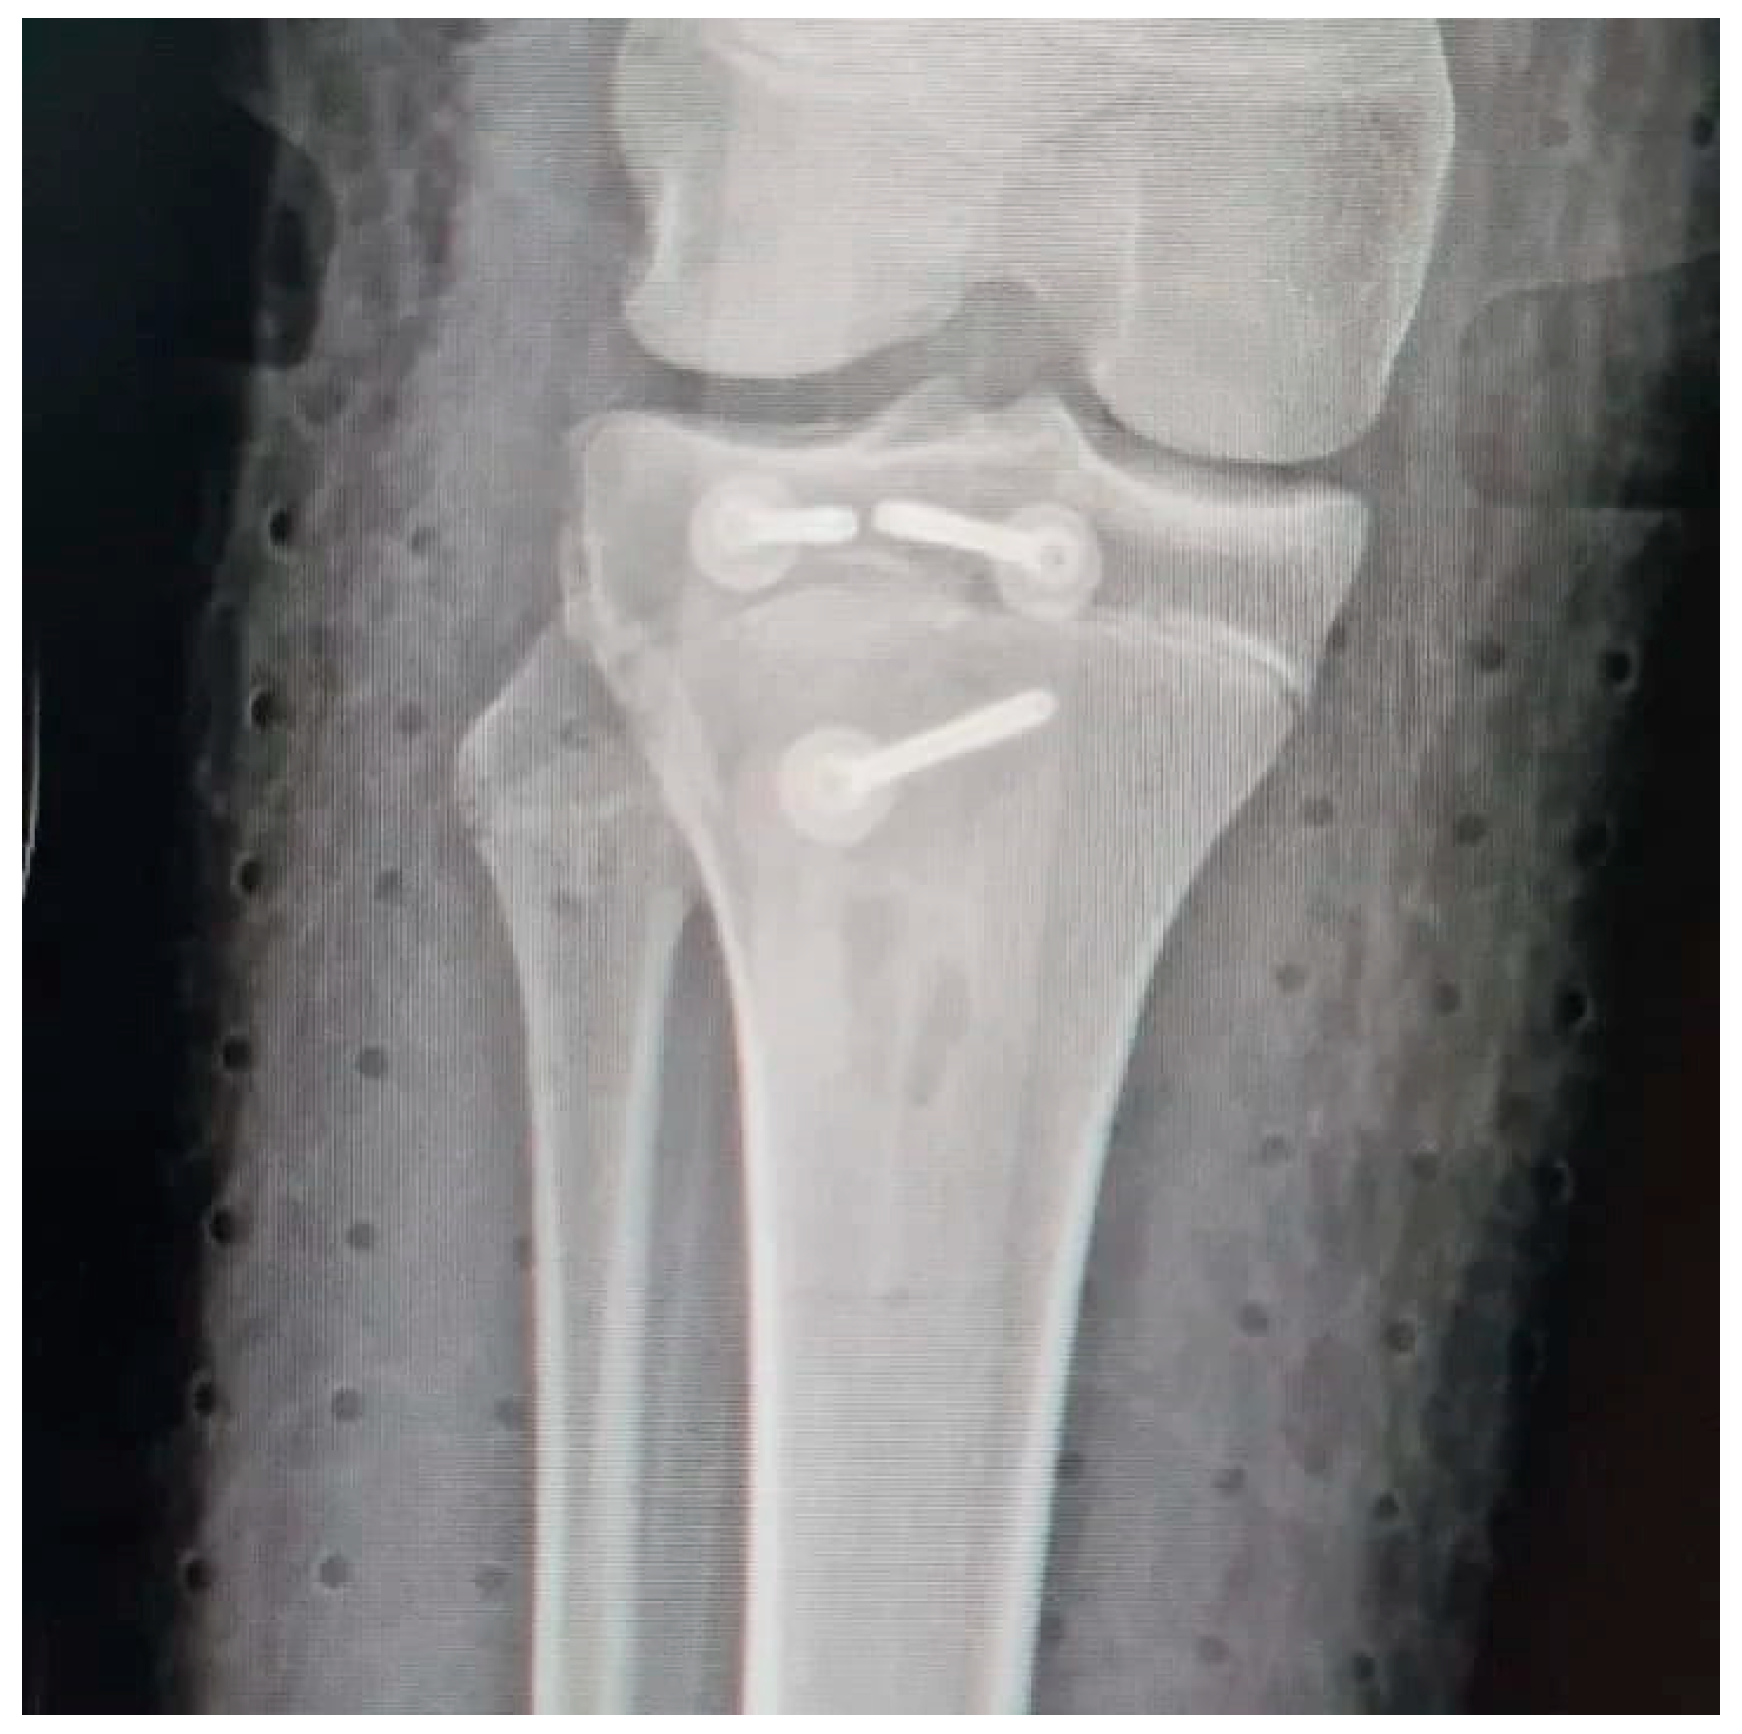

Tibial Tubercle Avulsion Fracture in Young Athletes Surgically Treated: Mid-Long Term Result and Comparison

2.3. Surgical Treatment and Complications